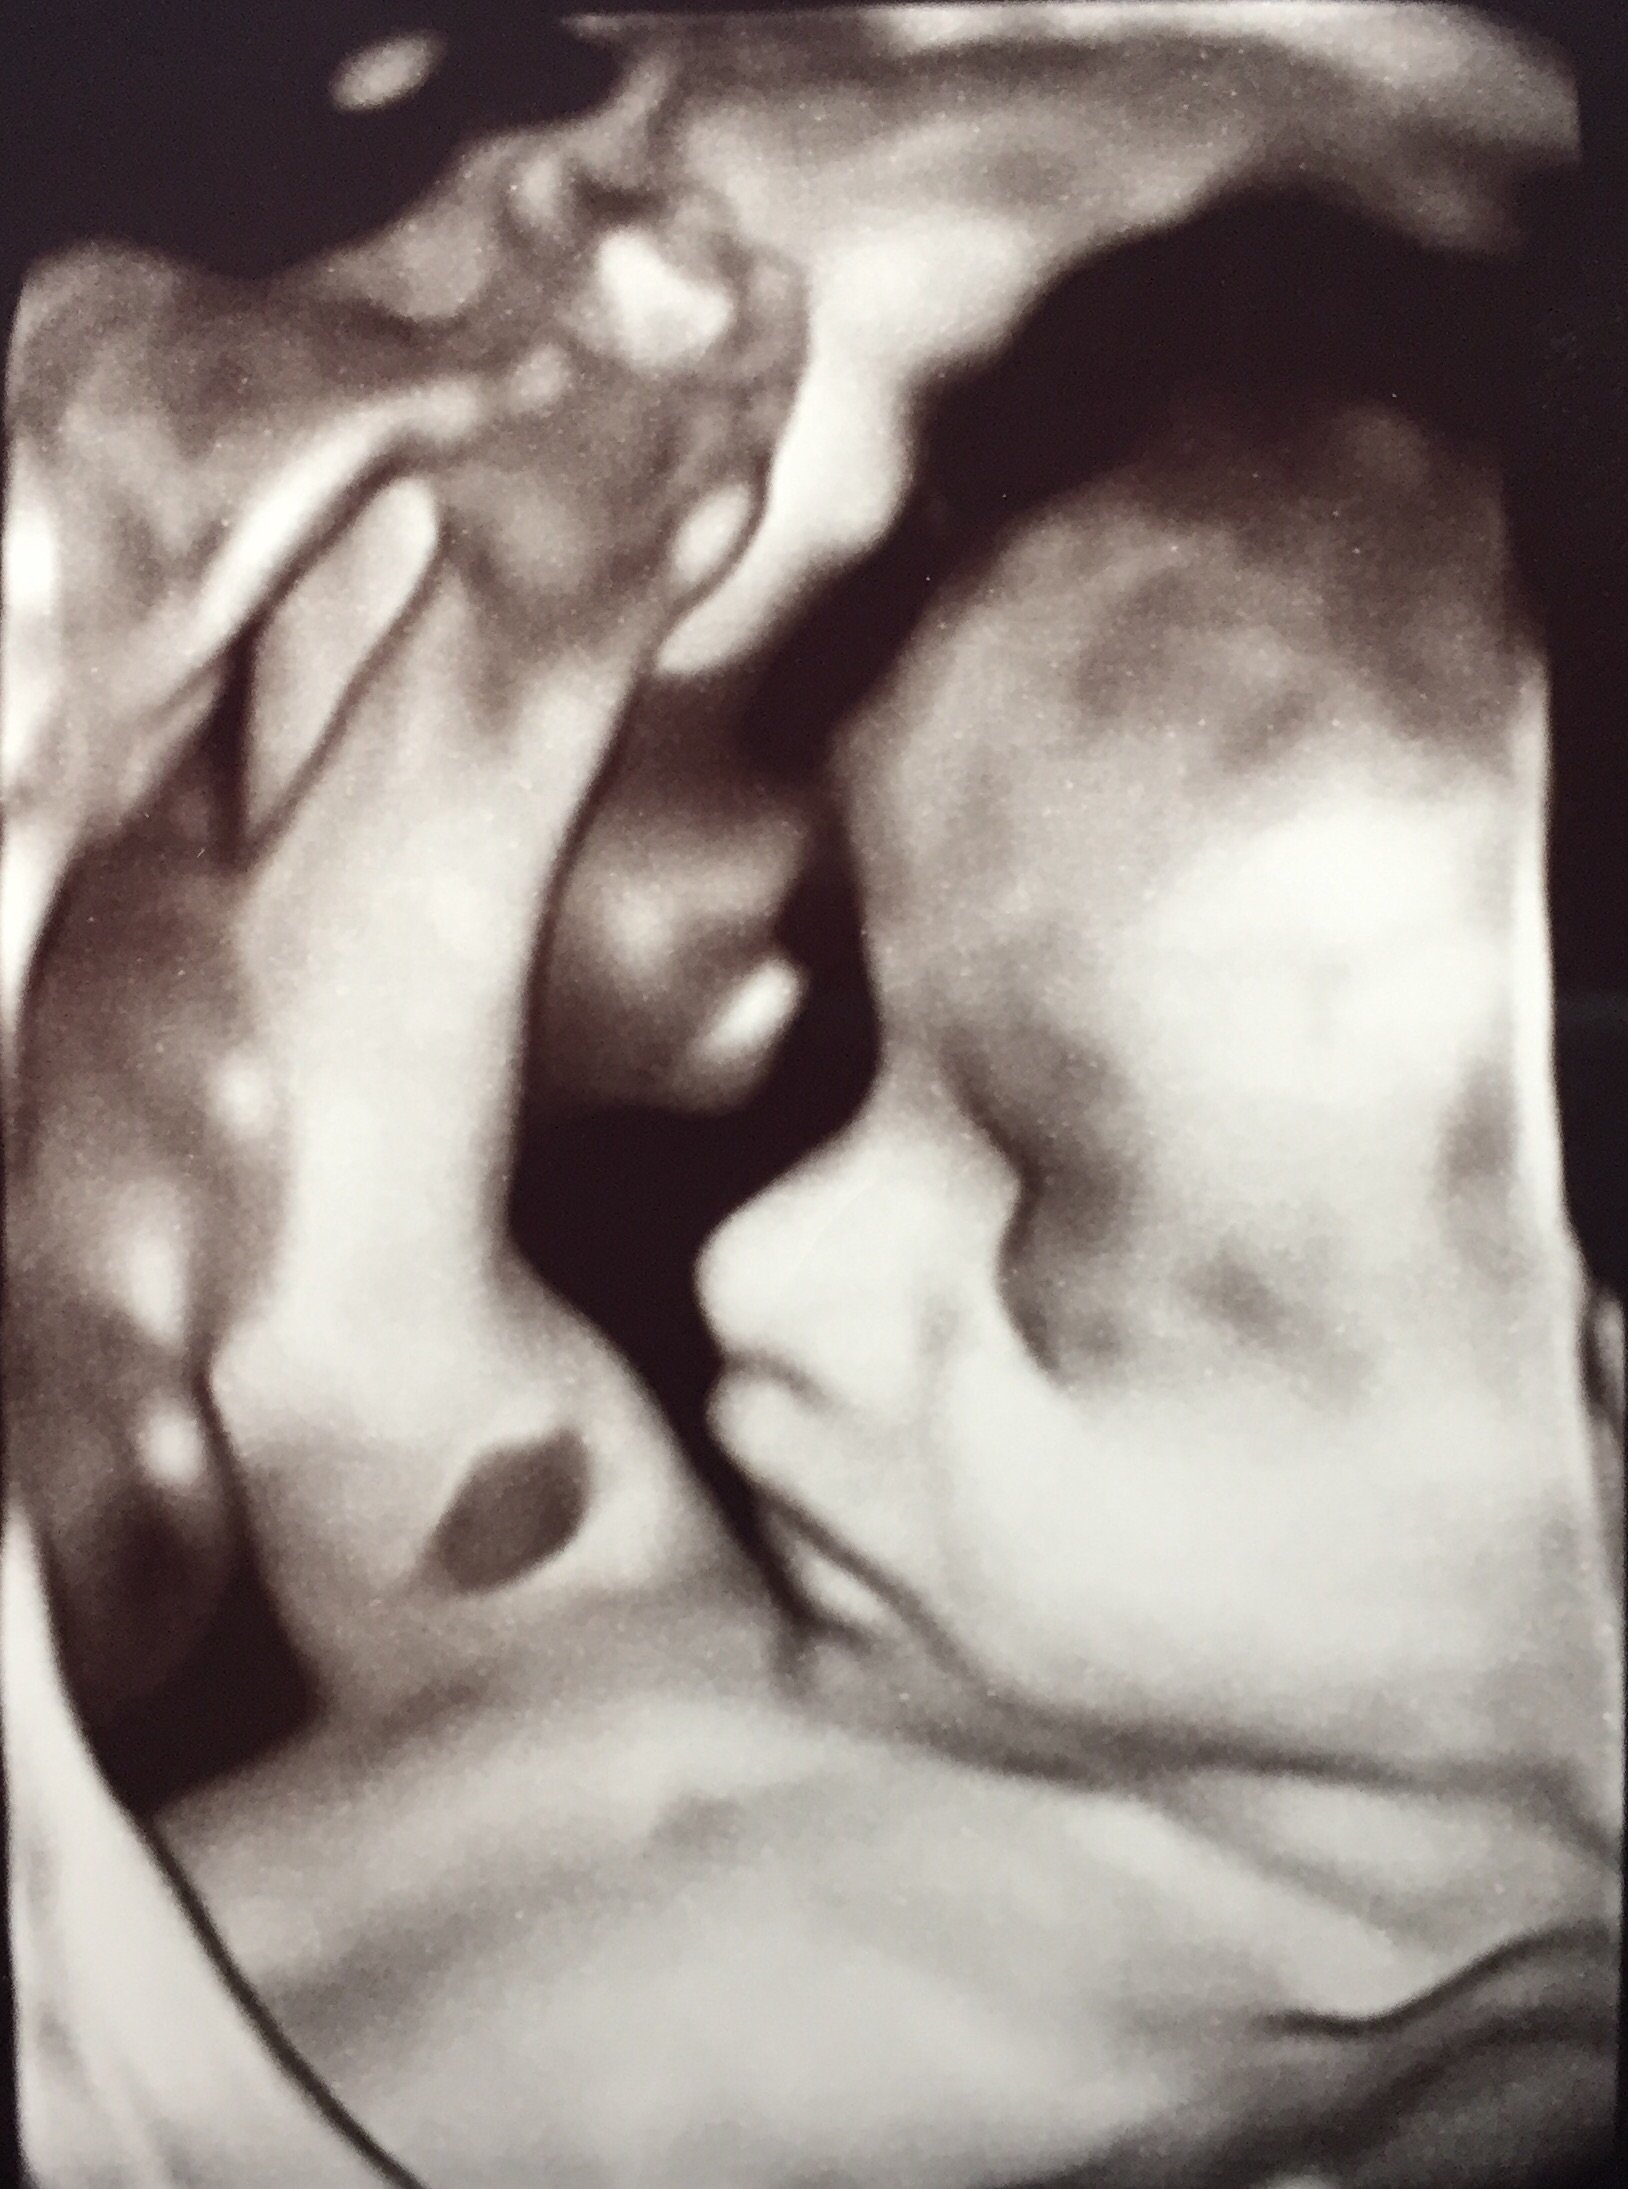

I feel the same way! I'm a photo junkie for sure and I too have been disappointed with ultrasounds pics of LO. I got good shots from my 20 week anatomy scan (below), but that's it from the whole pregnancy so far. I've had to ask for 2 out of the 3 other ultrasounds I've had and one of she she was just an embryo lol. The two I asked for are hard to see her. My MIL bought me a session so her, my mom, myself and my husband could go and see her sweet little face together for the holidays.

• I had mine done at 28 weeks...she was blowing kisses...mine was $105...it was worth it for me...memories are so great...